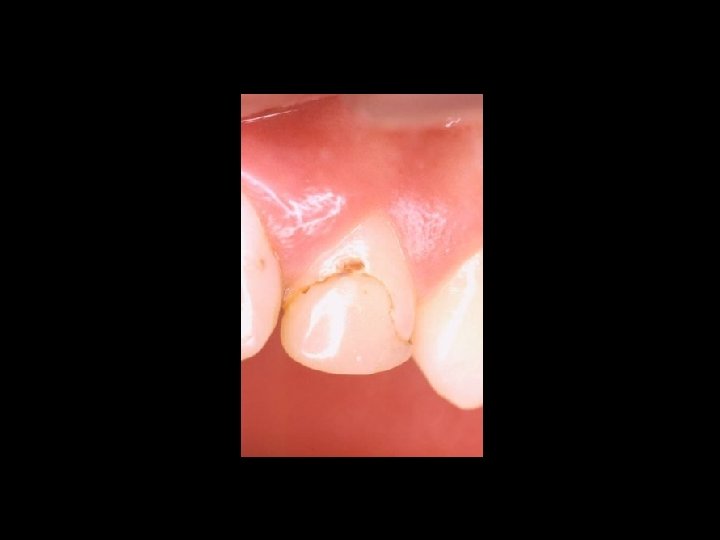

Responsabilità Ø Restauro della corona del dente Ø Trattamenti radicolari